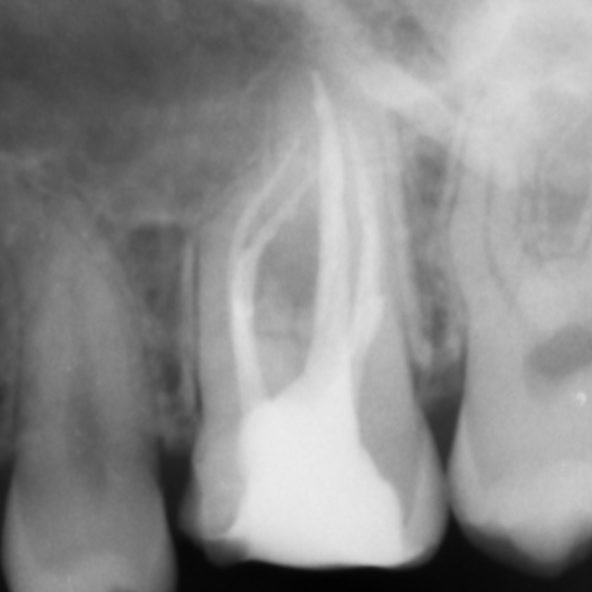

There are often multiple ports of communication between MB1 and MB2. The MB2 can join MB1 along its path or terminate via a separate apical foramen (Figures 1 and 2). Rarely, there can be an MB3 canal present (Figure 3).

Figure 1: MB1 and MB2 are two separate canals.

- Preoperative radiograph

- Mid-fill radiograph showing MB1 and MB2 are completely separate canals with individual apical foramen; both canals have acute apical curvatures

- Postoperative radiograph; a lateral canal was noted in the palatal canal.